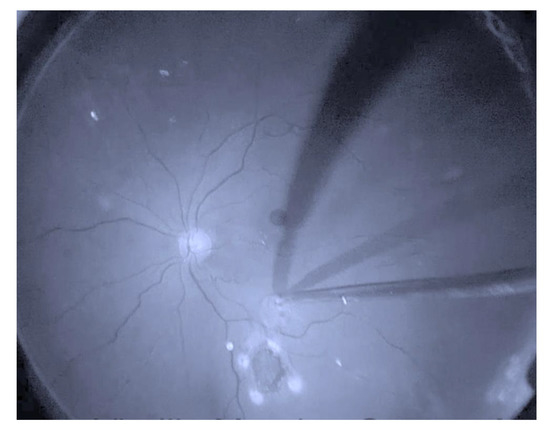

2.3. Surgical Procedures

- Tabandeh, H. Vascularization and Reperfusion of Autologous Retinal Transplant for Giant Macular Holes. JAMA Ophthalmol. 2020, 138, 305–309. [Google Scholar] [CrossRef]

- Wu, A.-L.; Chuang, L.-H.; Wang, N.-K.; Chen, K.-J.; Liu, L.; Yeung, L.; Chen, T.-L.; Hwang, Y.-S.; Wu, W.-C.; Lai, C.-C. Refractory macular hole repaired by autologous retinal graft and blood clot. BMC Ophthalmol. 2018, 18, 1–6. [Google Scholar] [CrossRef] [PubMed]

- Moysidis, S.N.; Koulisis, N.; Adrean, S.D.; Charles, S.; Chetty, N.; Chhablani, J.K.; Cortes, J.C.; Embabi, S.N.; Gordon, C.; Gregori, N.; et al. Autologous Retinal Transplantation for Primary and Refractory Macular Holes and Macular Hole Retinal Detachments: The Global Consortium. Ophthalmology 2021, 128, 672–685. [Google Scholar] [CrossRef] [PubMed]

- Tanaka, S.; Inoue, M.; Inoue, T.; Yamakawa, T.; Uchio, E.; Grewal, D.; Mahmoud, T.H.; Kadonosono, K. Autologous retinal transplantation as a primary treatment for large chronic macular holes. Retina 2019, 40, 1938–1945. [Google Scholar] [CrossRef]

- Chang, Y.-C.; Liu, P.-K.; Kao, T.-E.; Chen, K.-J.; Chen, Y.-H.; Chiu, W.-J.; Wu, K.-Y.; Wu, W.-C. Management of refractory large macular hole with autologous neurosensory retinal free flap transplantation. Retina 2020, 40, 2134–2139. [Google Scholar] [CrossRef]